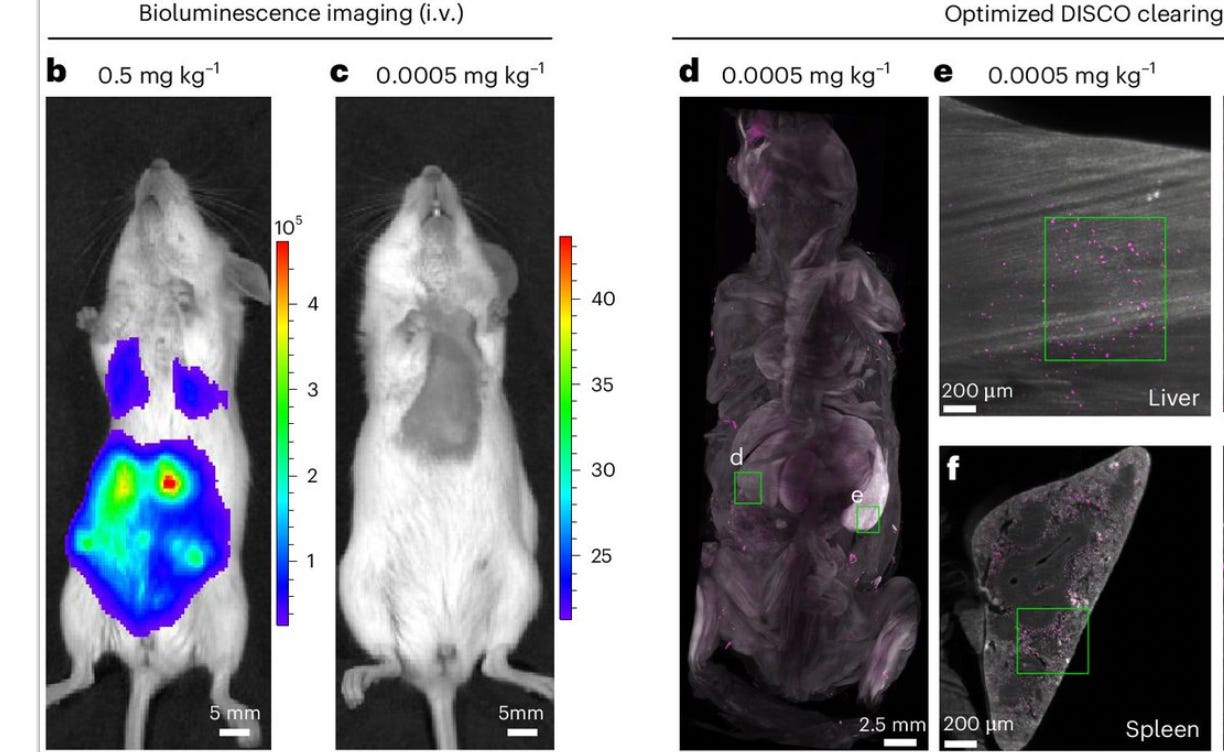

The peer-reviewed study published yesterday in the prestigious Nature Biotechology, titled “Nanocarrier imaging at single-cell resolution across entire mouse bodies with deep learning.” It had forty authors. There’s safety in numbers. They cautiously avoided criticizing the covid shots directly, but the implications were unavoidable.

This study investigated lipid nanoparticles (LNPs), which are the tiny globs of fake fat that deliver mRNA into cells. They tracked the LNPs’ distribution and effects throughout the body—which they found far beyond the injection site. The researchers found that even at very low doses, LNPs wander far afield and worse, they accumulate in unintended organs, triggering immune disregulation and metabolic disturbances.

The study’s carefully documented conclusion upended the government’s original claims the mRNA vaccines would remain “localized at the injection site” (i.e. that they’d quickly and harmlessly dissolve in your shoulder). The findings also provided a plausible explanation for what causes serious known side effects like myocarditis.

These findings aren’t altogether new. They align with earlier findings from a widely ignored 2022 Japanese biodistribution study. The difference now, though, is these scientists used cutting-edge imaging technology to track LNPs in mice, and they used A.I. to analyze very complex data sets (such as systemic effects with multiple variables) and for modeling simulations at various LNP dosages.